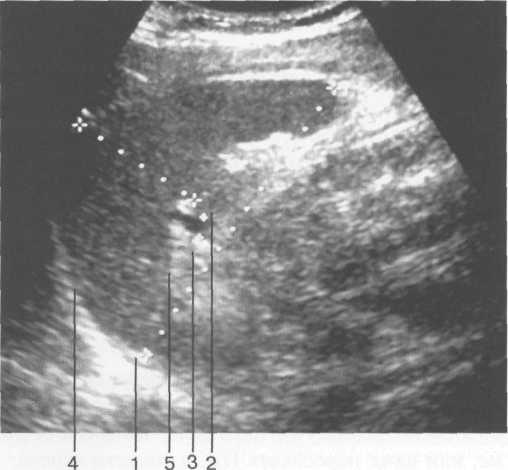

Рис. 11.23. УЗИ селезенки, продольное сканирование.

1 — длина селезенки; 2 — толщина селезенки; 3 — селезеночная вена в воротах селезенки; 4 — верхняя (диафрагмальная) поверхность; 5 — нижняя поверхность.

Для изучения размеров селезенки (в том числе в динамике) предложено определять селезеночный индекс, величина которого является произведением расстояния от ворот селезенки до ее переднего полюса и толщины органа на уровне ворот. В норме селезеночный индекс не превышает 20 см 2 .

Селезеночная вена в норме визуализируется в виде анэхогенной полосы, диаметр ее не зависит от возраста, но обычно не превышает 7 мм.

Паренхима селезенки имеет однородную мелкозернистую структуру, обладает эхогенностью ниже печени, но несколько выше чем у коркового вещества почки. Капсула селезенки представлена в виде линейного гиперэхогенного слоя, интенсивность которого увеличивается с возрастом за счет склерозирования, что особенно заметно у пациентов старше 60 лет (рис. 11.23).